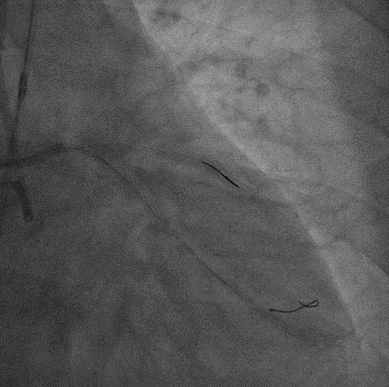

PCI过程

7F XB3.5,Cosair,Runthrough中间支保护,Pilot200正向进入D1,Pilot200 无法通过病变,交换Judo导丝

更换Judo3顺利到达LAD远端,Cosair跟进交换Runthrough

Ballon 2.0*15mm Dilatation & IVUS check

LAD-LM DES 2.75*20mm,2.75*18mm,3.0*30mm

Ballon 2.0*15mm Dilatation for D1 Ostial

NC Ballon & IVUS check

Final result:TIMI3